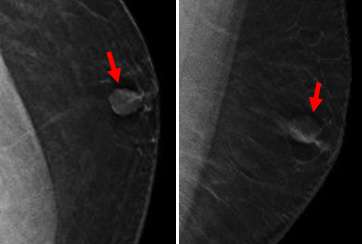

Case: Malignant Male Breast Lesions Figure 1

Figure 1: 38 yo M with breast lump. Mammogram (CC, left and MLO, right) demonstrated an oval mass in the left breast retroareolar region.